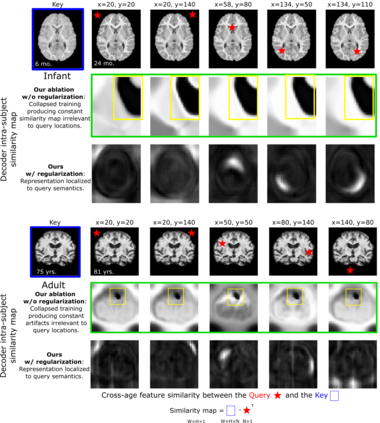

Recent self-supervised advances in medical computer vision exploit global and local anatomical self-similarity for pretraining prior to downstream tasks such as segmentation. However, current methods assume i.i.d. image acquisition, which is invalid in clinical study designs where follow-up longitudinal scans track subject-specific temporal changes. Further, existing self-supervised methods for medically-relevant image-to-image architectures exploit only spatial or temporal self-similarity and only do so via a loss applied at a single image-scale, with naive multi-scale spatiotemporal extensions collapsing to degenerate solutions. To these ends, this paper makes two contributions: (1) It presents a local and multi-scale spatiotemporal representation learning method for image-to-image architectures trained on longitudinal images. It exploits the spatiotemporal self-similarity of learned multi-scale intra-subject features for pretraining and develops several feature-wise regularizations that avoid collapsed identity representations; (2) During finetuning, it proposes a surprisingly simple self-supervised segmentation consistency regularization to exploit intra-subject correlation. Benchmarked in the one-shot segmentation setting, the proposed framework outperforms both well-tuned randomly-initialized baselines and current self-supervised techniques designed for both i.i.d. and longitudinal datasets. These improvements are demonstrated across both longitudinal neurodegenerative adult MRI and developing infant brain MRI and yield both higher performance and longitudinal consistency.